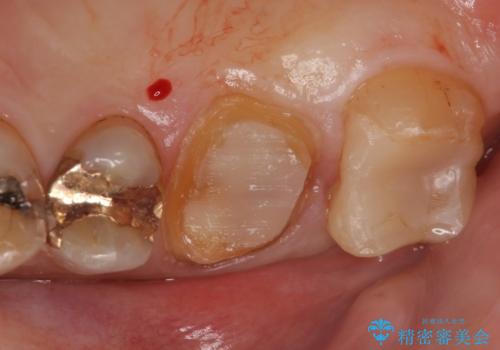

その後歯茎の回復を待ち、オールセラミッククラウンおよびセラミックインレーによる補綴・修復を行いました。

当院のセラミックインレーはemaxという強度と審美性に優れた材料を使用しています。

またプレス方式でインレーを製作しているため、削り出しで製作するCADCAMより優れた適合性も持ち合わせており、虫歯が再発しにくい修復物です。

今回用いたオールセラミッククラウンはジルコニアフレームという白い素材の上にセラミックを盛っているため、審美性が非常に高いのが特徴です。

また、ジルコニアは人工ダイヤモンドの材料にも使われているほど高い強度を持っており、そのためオールセラミッククラウンは審美性だけでなく、奥歯やブリッジの補綴も可能とするクラウンです。